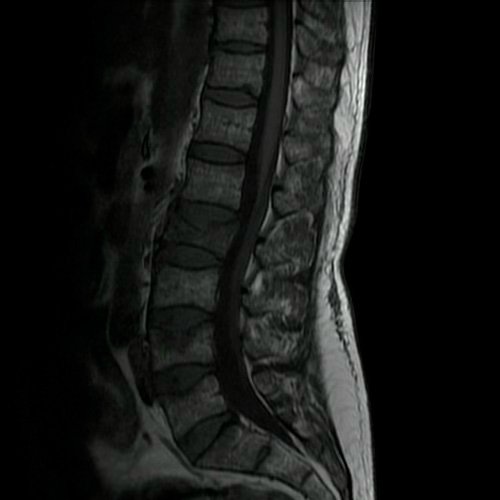

- Resonancia magnética de columna lumbar (28/08/2025): fractura aplastamiento de L2, a expensas de su platillo superior, que compromete el 60% de su altura. Fractura aplastamiento de L4 y L5, a expensas de platillos superiores, que afecta menos del 30% de la altura del cuerpo vertebral, sin desplazamiento. Estos cuerpos vertebrales presentan impronta de Schmorl en la placa terminal superior y resultan hiperintensos en STIR, hipointenso en T1, hallazgo compatible con edema óseo.

- Tomografía de columna lumbosacra (Día 0): Contamos con TC previa del día 04-09-2025 y RMI del día 28-08-2025. Hiperlordosis lumbar. Eje lumbar se encuentra desviado hacia la derecha. Persiste, de mayor jerarquía que en TC previa, la reducción de altura de los cuerpos vertebrales de D12, L2, mayor al 50%, con afectación del muro posterior. También se observa reducción del 30 % del cuerpo vertebral L4 y L5. Hallazgos en relación a fracturas aplastamiento patológicas. Además se observa marcada osteopenia generalizada. Disminución de la altura intervertebral de L2-L3 y L3-L4, a nivel de su margen posterior. Los demás espacios discales visualizados son de altura conservada. No se observan signos de protrusiones ni hernias discales. Ligera rarefacción del TCS paravertebral.